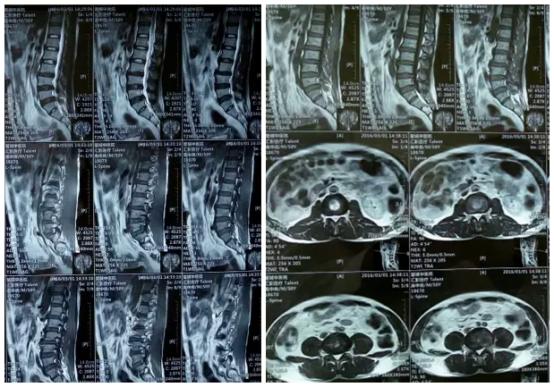

唐都医院脊柱神经外科王鹏教授结合患者病史、体征、症状及影像资料确诊为腰腰5-骶1(L5-S1)椎间盘突出症,建议手术治疗。

磁共振